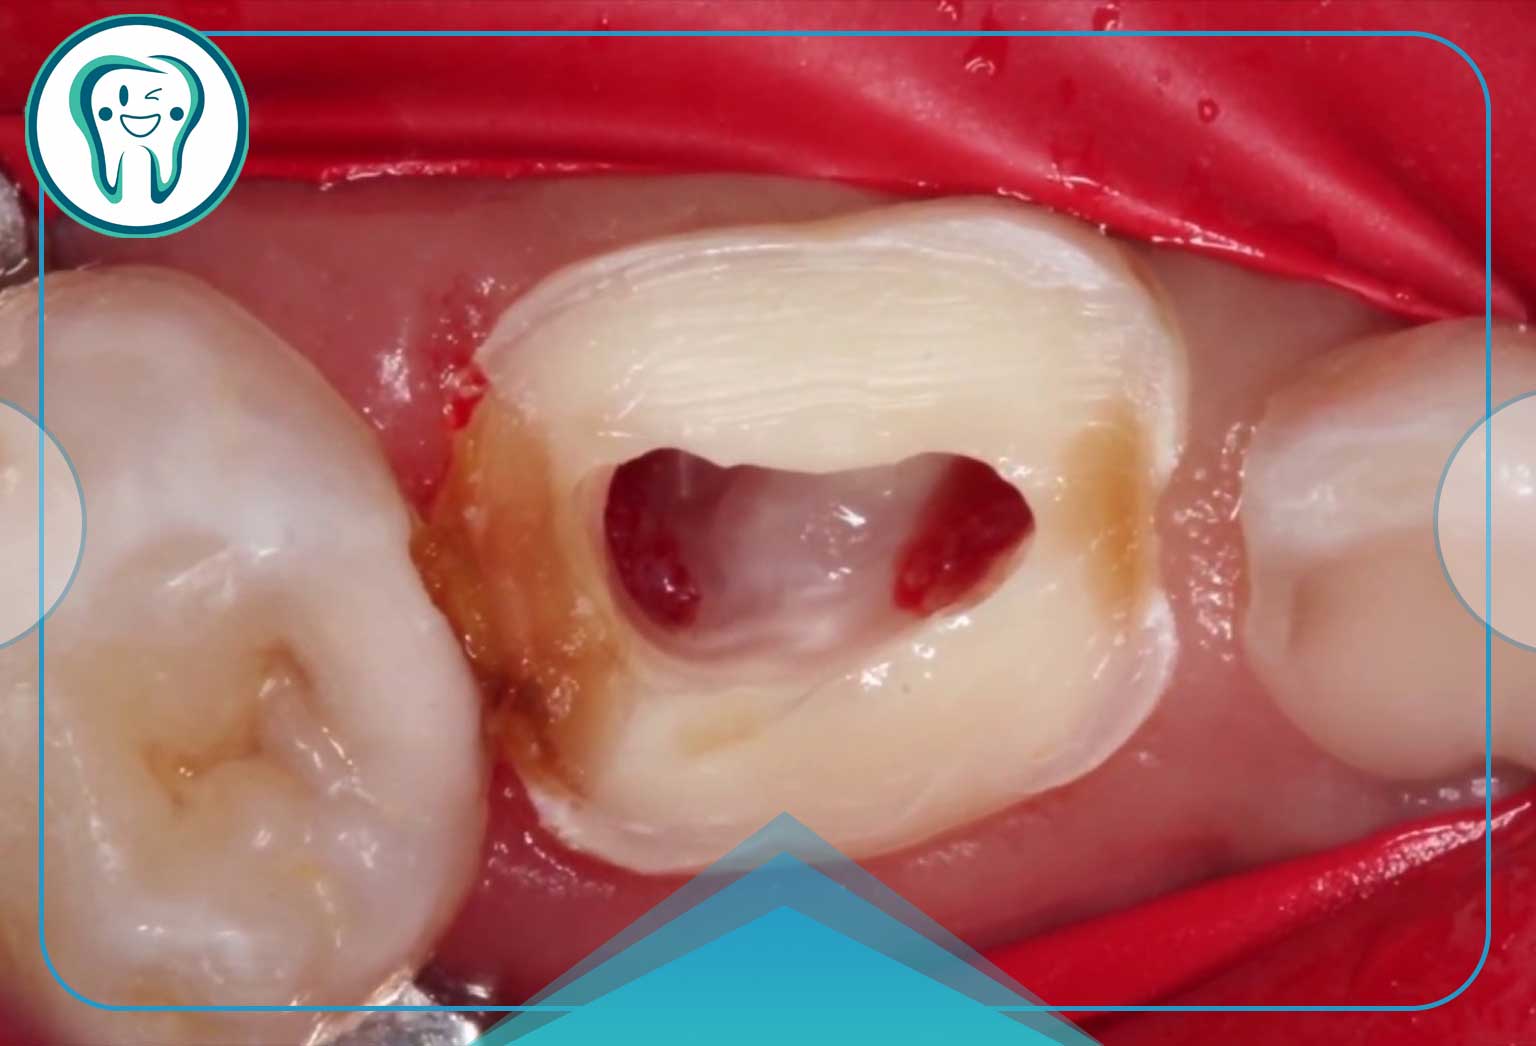

این روش رایجترین درمان برای دندان شیری است که پوسیدگی آن به پالپ رسیده اما هنوز عصب در قسمت ریشهای سالم است. هدف از پالپوتومی، حذف قسمت ملتهب و آلوده پالپ در تاج دندان (قسمتی که در معرض پوسیدگی قرار گرفته) و حفظ حیات پالپ در داخل کانالهای ریشه است.

- نحوه انجام: دندانپزشک بخش بالایی پالپ (که عصب در تاج دندان قرار دارد) را برمیدارد و با مادهای زیستسازگار (معمولاً متیلن بلو یا MTA) پانسمان میکند تا بافت سالم باقیمانده در ریشه تحریک به ترمیم شود. سپس روی دندان یک روکش (معمولاً روکش استیل یا زیرکونیا) قرار داده میشود تا از شکستگی دندان جلوگیری شود.

پالپکتومی (Pulpectomy) – درمان کامل ریشه

پالپکتومی در دندان شیری، معادل همان عصبکشی در دندان دائمی است، اما با یک تفاوت بسیار مهم: در دندان شیری، فضای کانال ریشه با مواد قابل جذب (Resorbable Material) پر میشود. این مواد باید همراه با جذب طبیعی دندان توسط بدن (آمادهسازی برای دندان دائمی) جذب شوند.

- نحوه انجام: تمام محتویات پالپ دندان، هم در تاج و هم در ریشهها، برداشته شده، کانالها ضدعفونی و سپس با مادهای مانند زینک اکساید یوجنول (ZOE) پر میشوند.